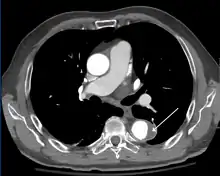

Computed tomography angiography is a fast, non-invasive test that gives an accurate three-dimensional view of the aorta. These images are produced by taking rapid, thin-cut slices of the chest and abdomen, and combining them in the computer to create cross-sectional slices. To delineate the aorta to the accuracy necessary to make the proper diagnosis, an iodinated contrast material is injected into a peripheral vein. Contrast is injected and the scan performed using a bolus tracking method. This type of scan is timed to injection to capture the contrast as it enters the aorta. The scan then follows the contrast as it flows through the vessel. It has a sensitivity of 96 to 100% and a specificity of 96 to 100%. Disadvantages include the need for iodinated contrast material and the inability to diagnose the site of the intimal tear.

CT with contrast demonstrating aneurysmal dilation and a dissection of the ascending aorta (type A Stanford)